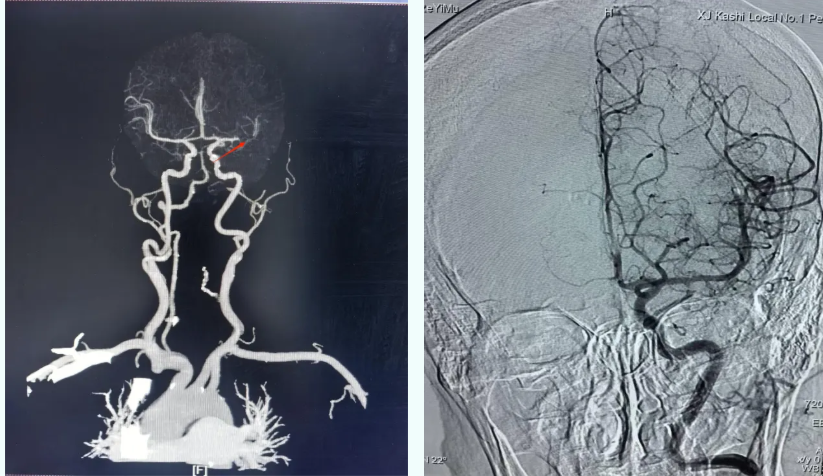

「卒中救治争的是分秒,每延误 1 分钟,可能导致近 190 万个脑细胞死亡。」在完成头颅 CT 排查,排除溶栓禁忌后,当地卒中团队于 20 时 40 分许给予静脉溶栓。但 1 小时后,患者症状缓解不明显,复查头颅 CT 血管成像(CTA)「左侧大脑中动脉闭塞」,提示为心源性栓塞,单纯溶栓效果有限,需尽快行机械取栓术。

导丝精准进入闭塞段,回旋取栓装置迅速释放,一次抽吸便顺利清除血栓。术后造影显示脑血流恢复良好,尼女士生命体征稳定。第二天查房时,尼女士已能进行基本交流,言语清晰、下肢活动明显改善,神经功能评分大幅提升。